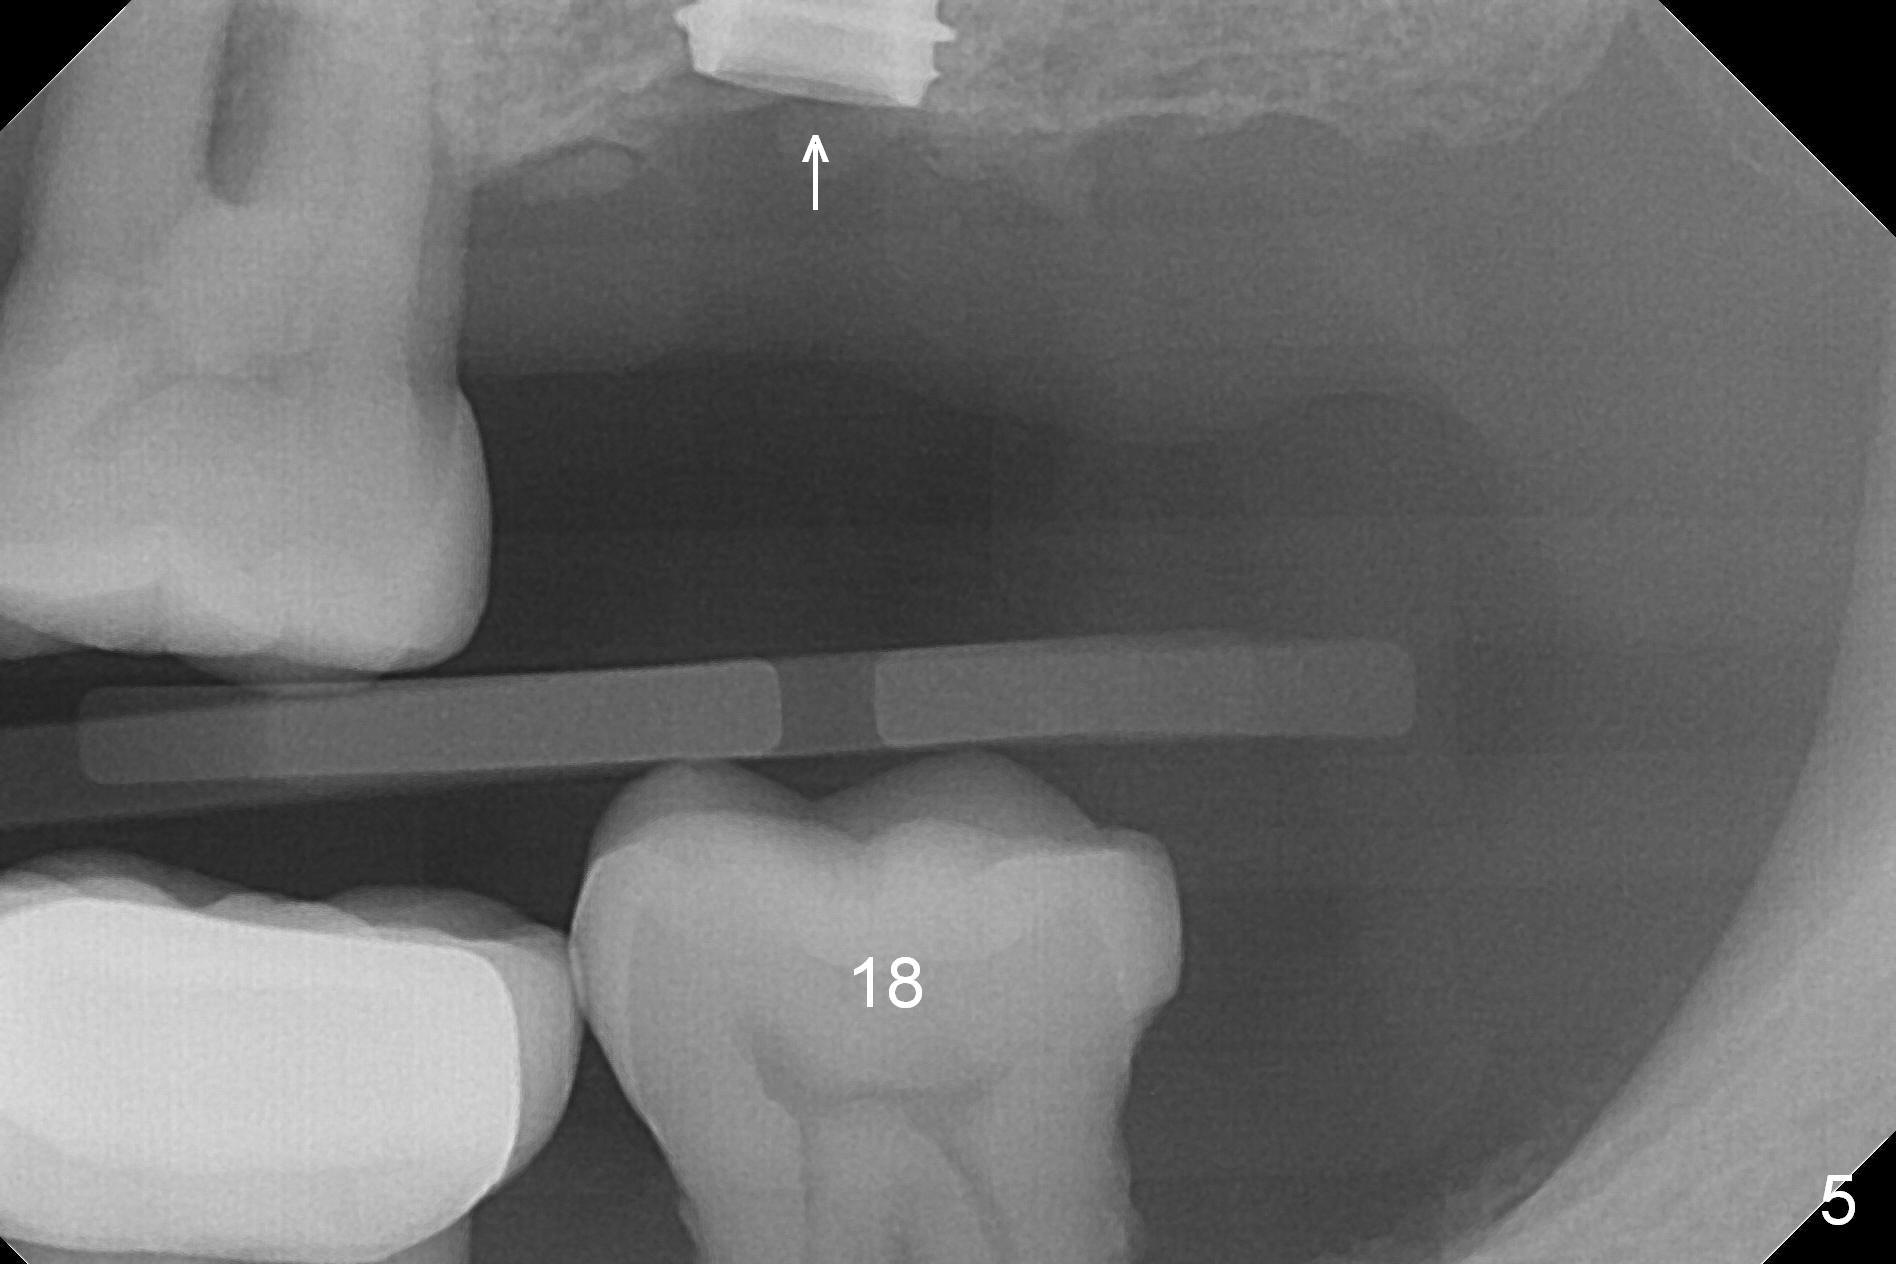

A 1.2 mm initial drill is used to start osteotomy at the site of #15 (Fig.1). After moving the osteotomy distally (with Lindamann bur), the osteotomy is enlarged by DIO Bone Expanders until 2.4/3.7 mm for 18 mm (gingival level) (Fig.2). Following the expander 3.0/4.4 mm, a 5x13 mm UF implant is placed supracrestal (Fig.3,4). After deepening the osteotomy with 3.8 mm drill for 3 mm, the implant is placed deeper by ~ 2 mm (Fig.5 arrow). Since the tooth #18 is supraerupted, a healing abutment (5.5x12(3) mm) is placed (Fig.6: H); the gingiva adapts to the abutment well. Suture is not necessary. The bone remains stable 2 and 4.5 months postop (Fig.7,8). Impression is taken. A crown is delivered nearly 6 months postop (08/07/2017). While there is minimal bone loss at #13 and 15 three years and 4 months post cementation, the tooth #14 and 18 are mobile (Fig.13,14, #13).